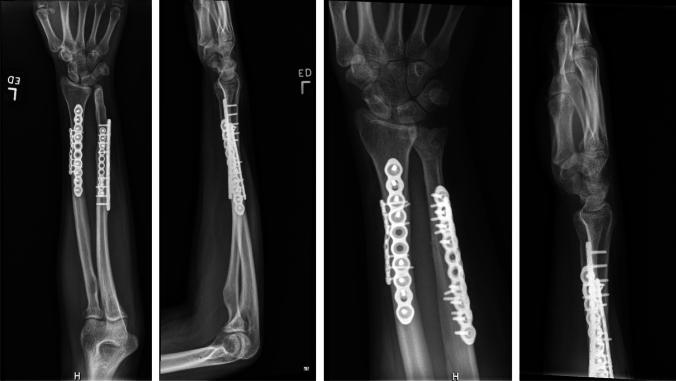

A 20-year-old pregnant female presented with an ulna fracture after a crush and bending type injury. Anatomic reduction of her ulna was not possible due to plastic deformation of the radius, requiring a corrective osteotomy of the radius. She is now 16 months out from surgery with full painless range of motion and radiographic union.

Plastic deformation of forearm fractures in adults is a rare phenomenon. It is possible that the patient's pregnancy contributed to her injury. Patients with uncommon fracture morphology can make operative intervention more complicated and necessitate additional procedures to achieve optimal motion and alignment.